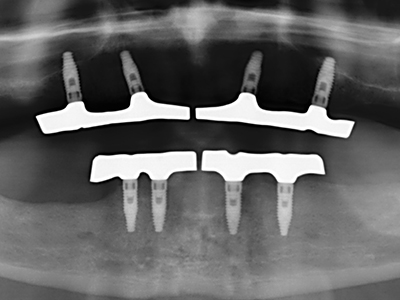

Както е показано в миналото, всяка костна хирургия представлява възможна индикация за пиезохирургия. По този начин, за препарацията на подвижни сегменти в остеогенеза (Фиг. 23-25) и остеотомия се използват специални накрайници, без да се застрашава снабдяването с кръв в кресталната зона, което е от съществено значение за успеха и на двете техники (Gonzalez-Garcia, Diniz-Freitas et al. 2008).

За отстраняването на имплант, вестибуларното костно покритие, което е заменено след премахване на импланта, може да бъде оформено, за да задържи контура на алвеоларния гребен.